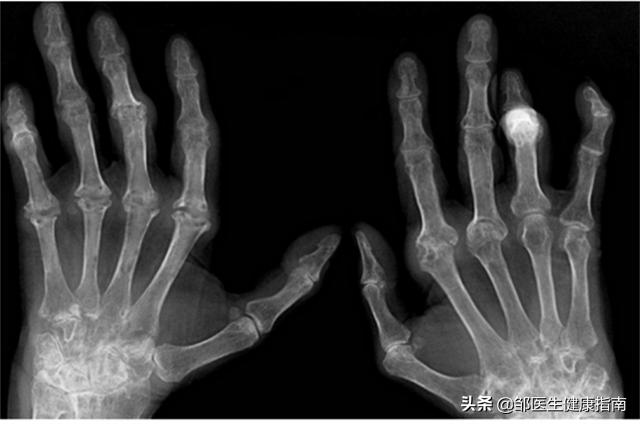

X线结果: 手指及腕关节的X线片显示关节周围软组织肿胀,关节端骨质疏松,关节间隙变窄。

4.骨肿瘤

骨肿瘤并不常见,仅可能在常规体检或是因为检查其他疾病时,在X线光片上偶然发现有骨肿瘤。如果出现临床症状的话,主要表现为 肿瘤病灶处发生疼痛或钝痛,运动时加剧 ,骨骼可肿胀或发生压痛、活动受限。